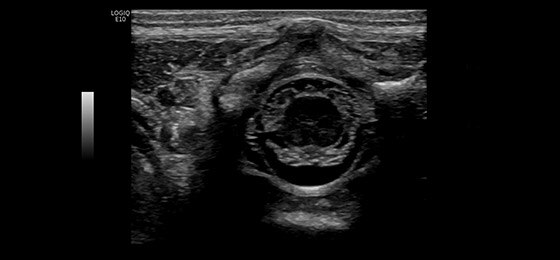

Benign Breast Mass with Multiple Calcifications, ML6-15-D